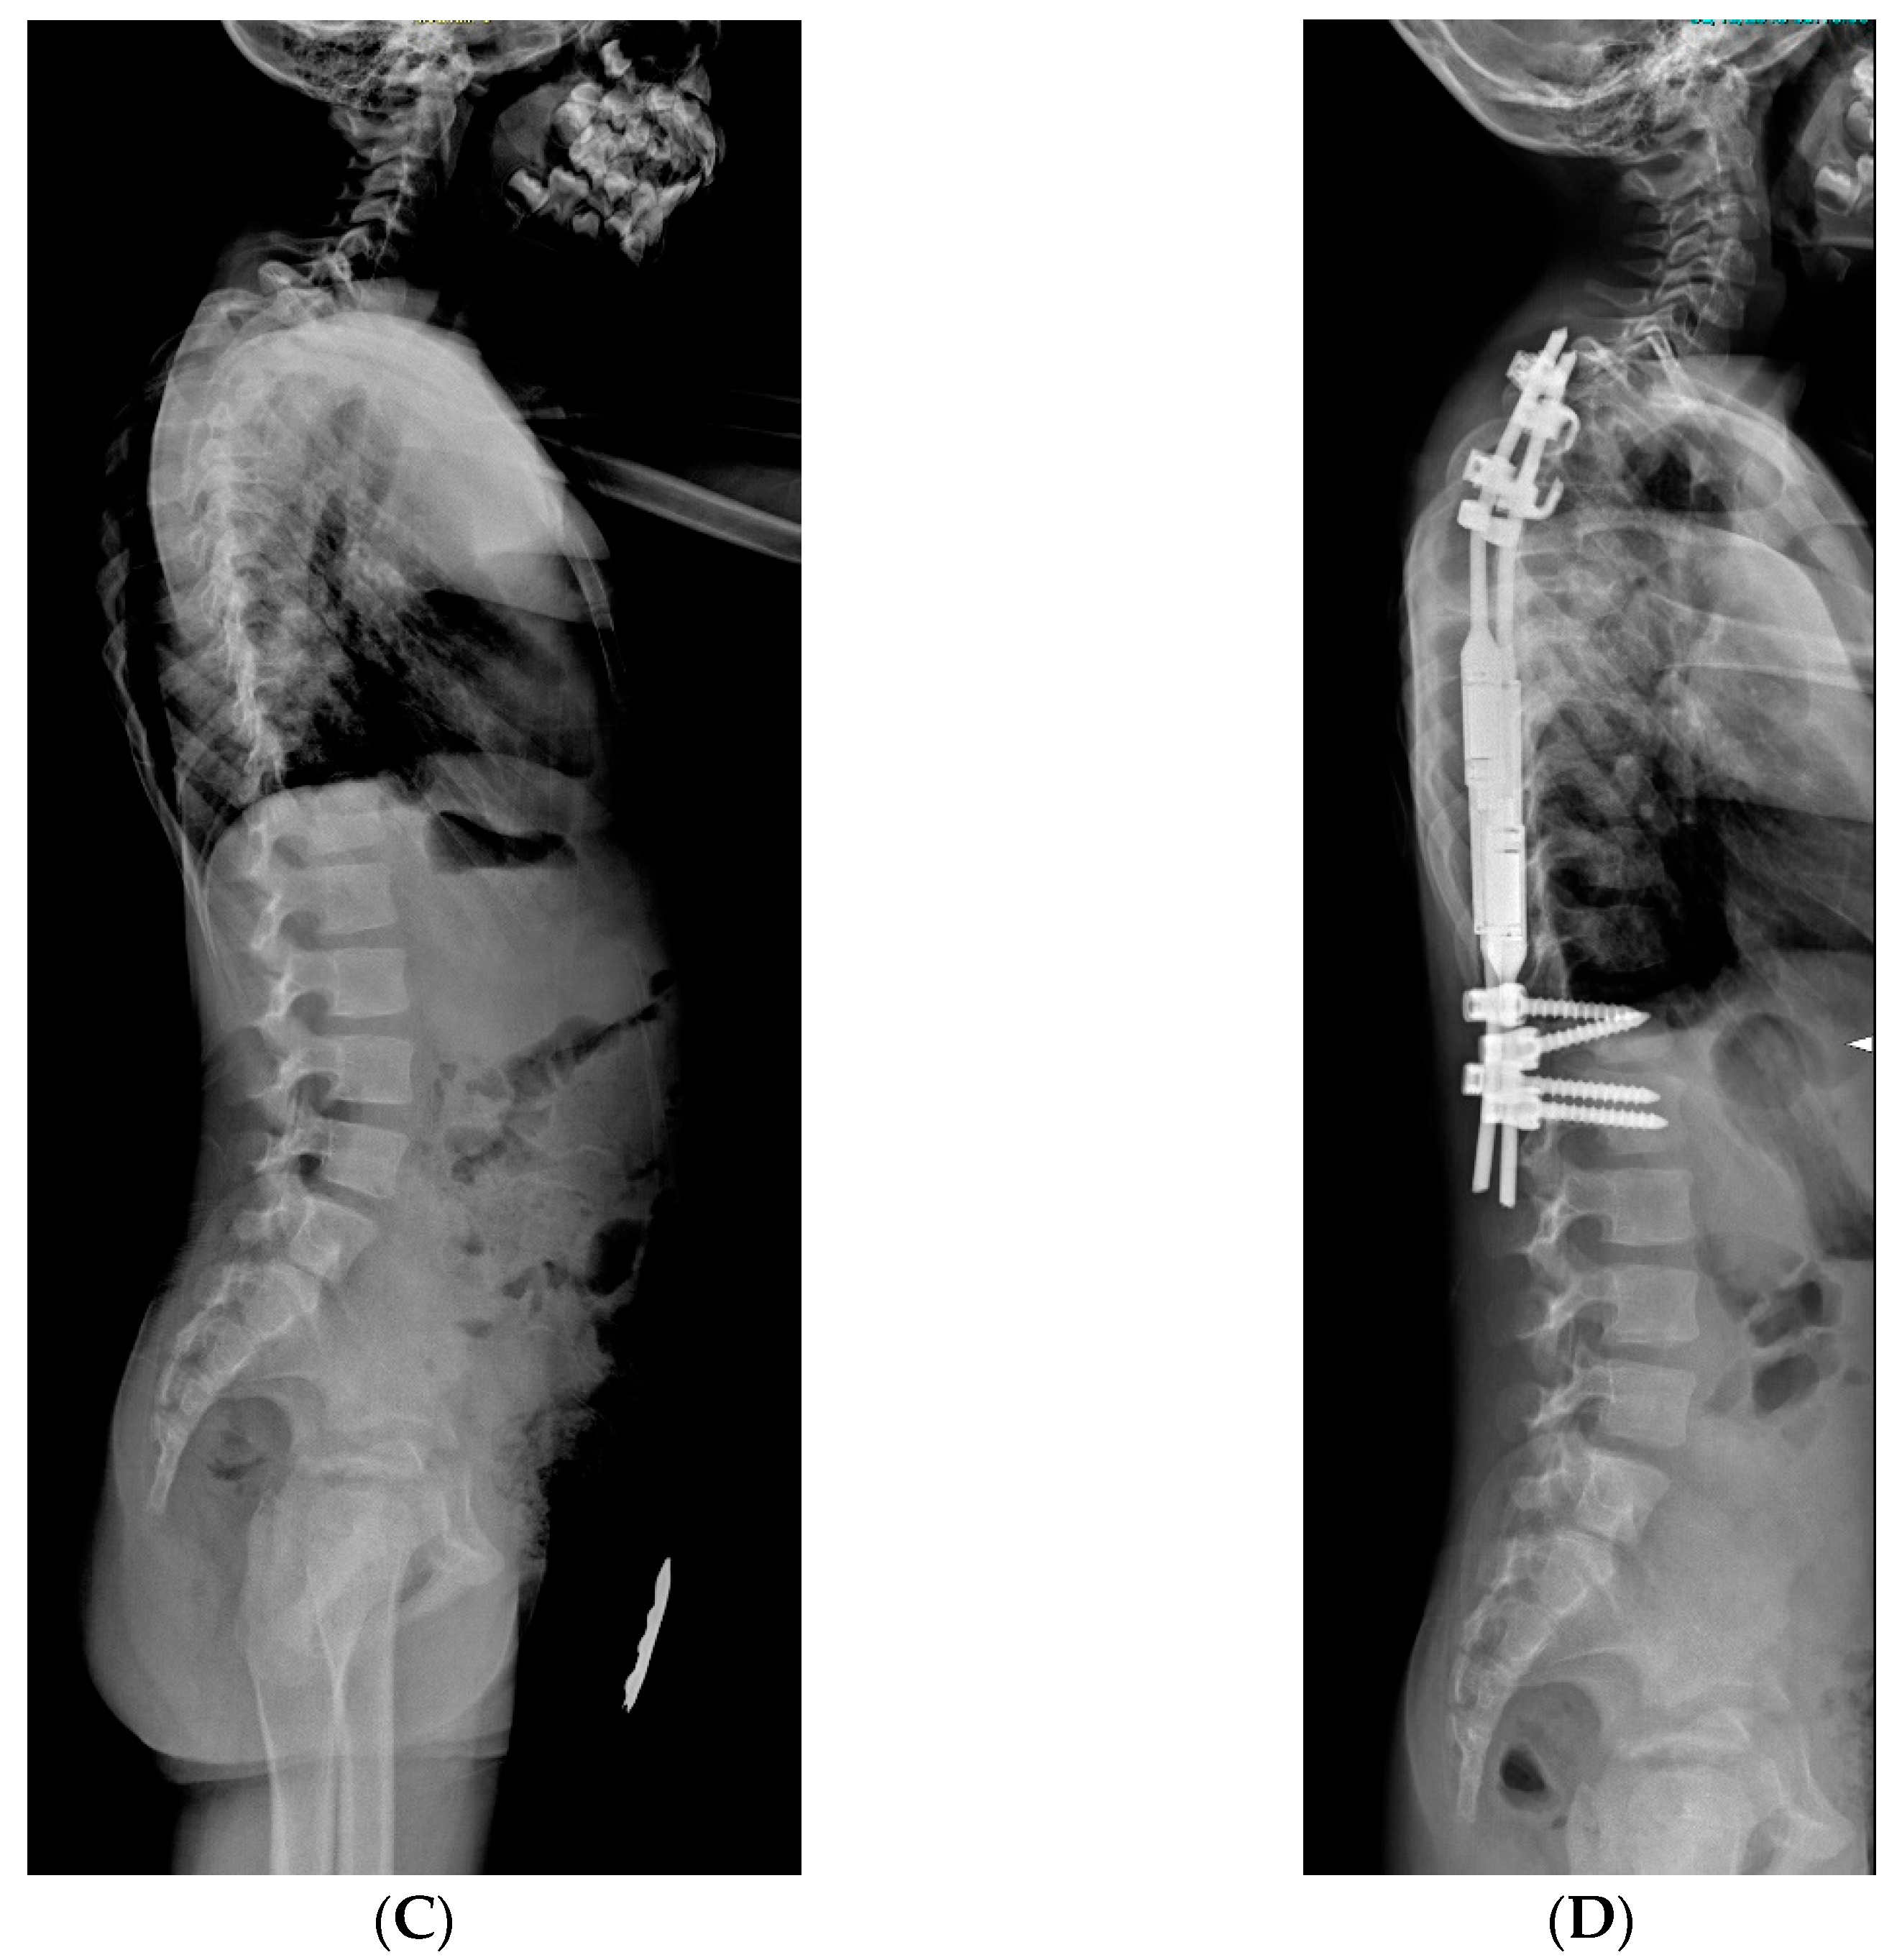

Figure 6.

X-rays of early onset scoliosis (EOS) corrected with vertical expandable prosthetic titanium rib (VEPTR): (A) pre-operative antero-posterior X-ray view; (B) post-operative antero-posterior X-ray view; (C) pre-operative lateral X-ray view; (D) post-operative lateral X-ray view.

VEPTR is a titanium alloy longitudinal rib distraction device. As with growth rods, repeated lengthenings are required [21]. The goal is to maximize thoracic volume and symmetry of the deformed thorax by lengthening the constricted hemithorax through a transverse opening wedge thoracostomy of the concave side [22], either through osteotomy of fused ribs or intercostal muscle lysis. The scoliosis is corrected indirectly by the thoracostomy, and the thoracic reconstruction is stabilized by the addition of a rib-to-spine or rib-to-pelvis VEPTR construct and another rib-to-rib VEPTR. No bracing is used postoperatively. VEPTRs are lengthened every four to six months. As 50% of the final thoracic volume depends on the growth between the age of 10 to 15 years, the final fusion is preferentially delayed until skeletal maturity (Figure 5 and Figure 6). When spinal deformity is associated with severe thoracic deformity, VEPTR is indicated. The main feature of this technique is that proximally, the bar is anchored to the ribs. Lengthening required surgery room, on average, every 12 months.